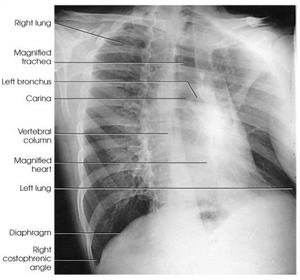

| Oblique Sternum | projection taken as LAO instead of RAO sternum is projected within the heart and scapula |

| RAO Sternum | inadequate breathing technique |

| Lateral Sternum | patient's left thorax is rotated anteriorly |

| Lateral Sternum | patient's right thorax is rotated anteriorly |

| PA Ribs Above Diaphragm Unilateral | patient rotated towards the right |

| PA Ribs Below Diaphragm Unilateral | Excessive obliquity |

| AP - LPO Ribs Above Diaphragm Unilateral | Insufficient obliquity |

| RAO Sternum | ANATOMY: jugular notch, SC joints, sternal body, and xiphoid process CRITERIA: sternum projected within heart shadow next to vertebral column POSITIONING: pt. rotated 15-20 degrees breathing technique CR perpendicular @ midsternum (2 fingers off downside spine) |

| Lateral Sternum | ANATOMY: manubrium, sternal body, and xiphoid in profile CRITERIA: 72'' SID reduces OID arms must be behind pt's back POSITIONING: CR perpendicular @ midsternum |

| AP/PA Ribs | ANATOMY: all ribs demonstrated 1-9 for upper 8-12 for lower CRITERIA: no motion/breathing POSITIONING: AP ribs when pt c/o posterior pain PA ribs when pt c/o anterior pain CR perpendicular @ T7 |

| Oblique Ribs | CRITERIA: 45 degree oblique will shift spine away from anatomy of interest LPO/RAO = left axillary ribs RPO/LAO = right axillary ribs ribs 1-9 are seen on above diaphragm projections ribs 8-12 see on below diaphragm projections CR perpendicular @ T7 |